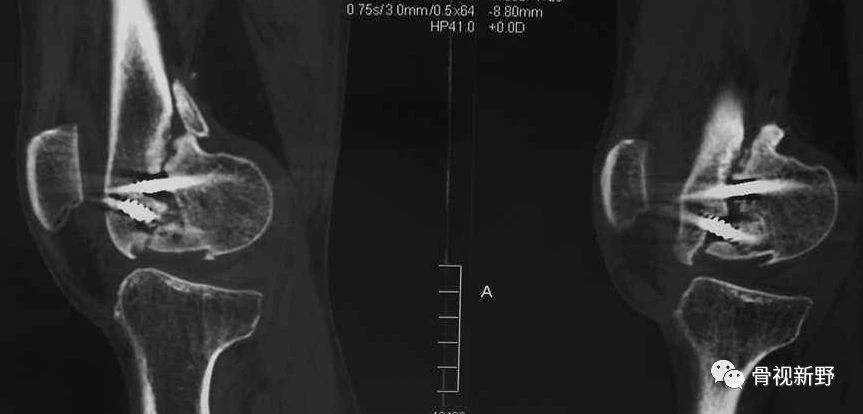

CT扫描在矢状位、轴位容易发现骨折及骨折线的走形方向